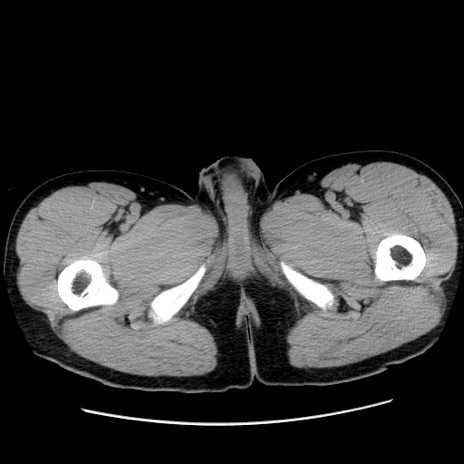

症例36(横断像)

【症例】20歳代 男性

【主訴】心窩部痛

【現病歴】今朝より上腹部痛あり。一旦軽快していたが再度出現したため救急要請。昨日夕に白身の魚を含む刺身を食べた。

【身体所見】BP 136/89mmHg、HR 74/min、BT 37.0℃、腹部:膨満、軟、心窩部に圧痛あり。反跳痛なし、筋性防御なし、腸雑音やや亢進あり。

【データ】WBC 17700、CRP 0.48